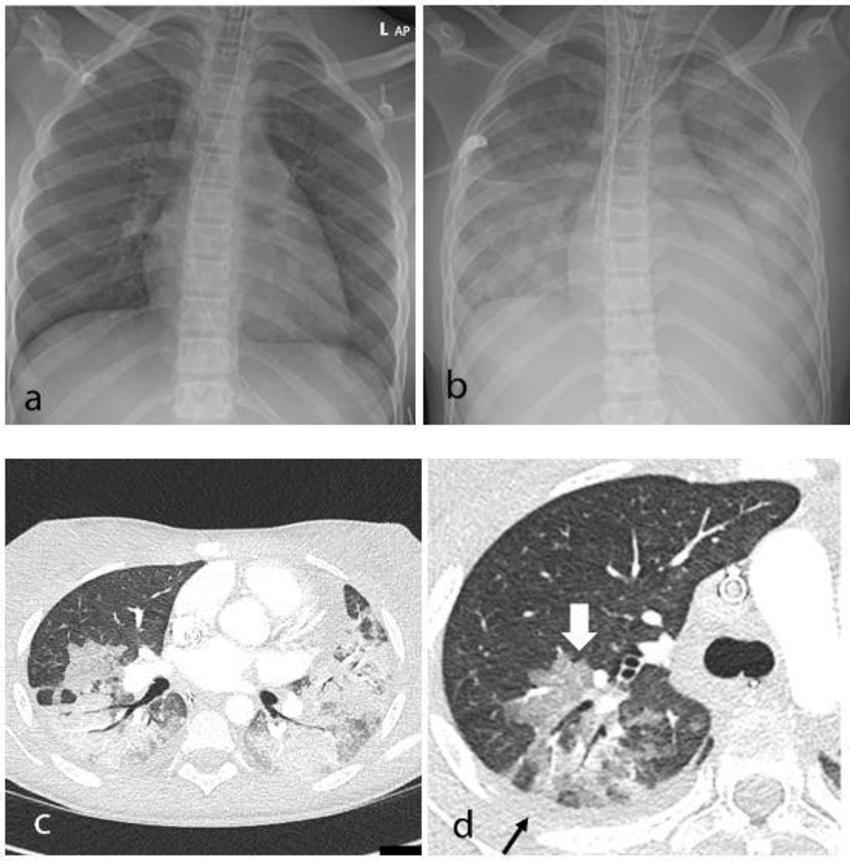

Figure 1. Thoracic findings in a 15-year-old girl with Multisystem Inflammatory Syndrome in Children (MIS-C). (a) Chest radiograph on admission shows mild perihilar bronchial wall cuffing. (b) Chest radiograph on the third day of admission demonstrates extensive airspace opacification with a mid and lower zone predominance. (c, d) Contrast-enhanced axial CT chest of the thorax at day 3 shows areas of ground-glass opacification (GGO) and dense airspace consolidation with air bronchograms. (c) This conformed to a mosaic pattern with a bronchocentric distribution to the GGO (white arrow, d) involving both central and peripheral lung parenchyma with pleural effusions (black small arrow, d).

High-res (TIF) version